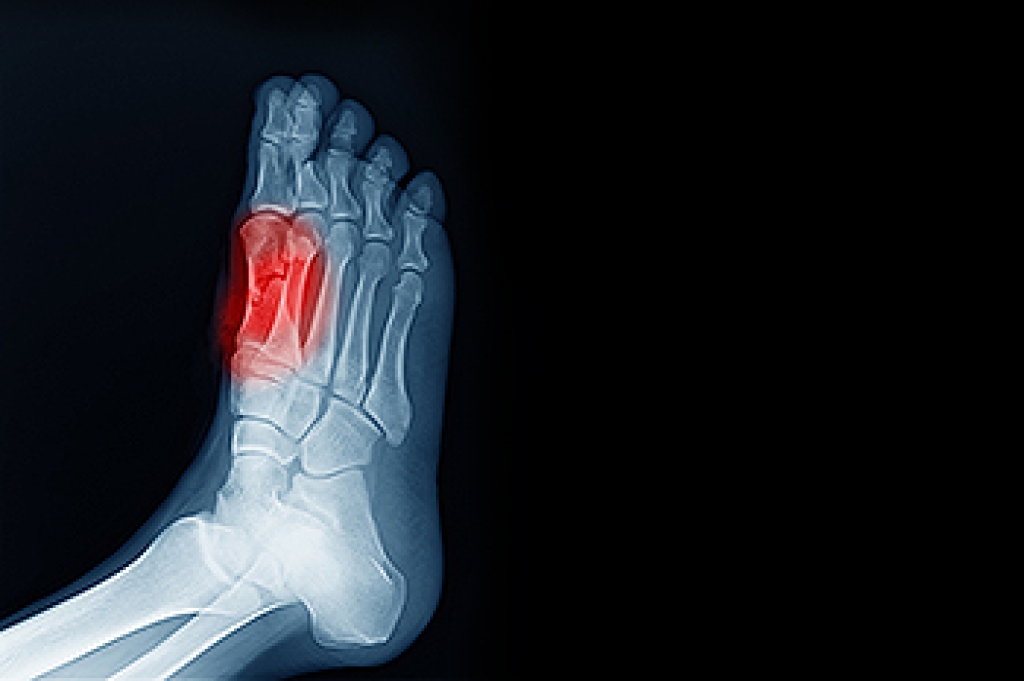

Swollen feet can also be caused by bone and tendon conditions, including fractures, arthritis, and tendinitis. Additionally, there may be skin and toenail conditions and an infection may cause the feet to swell. Patients who take medicine to treat high blood pressure may be prone to getting swollen feet.